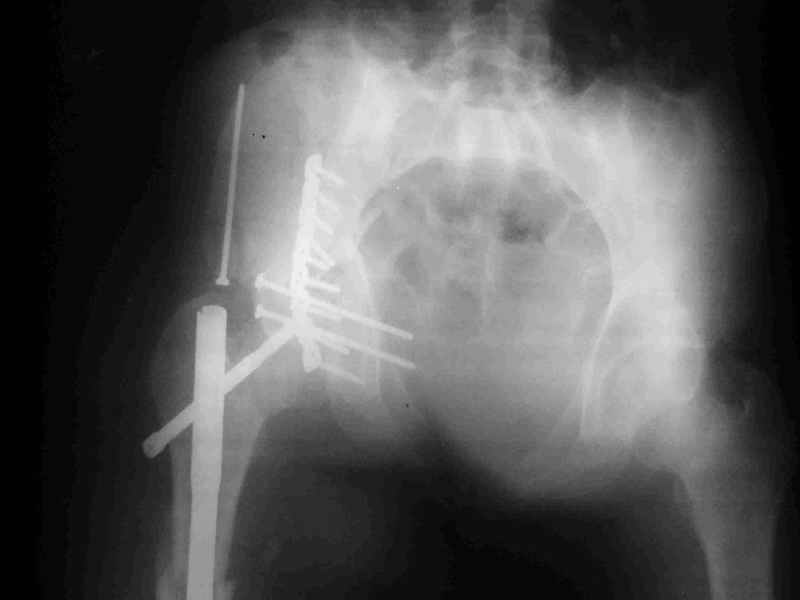

Уважаемые коллеги,Мужчина 36 лет от роду попал в ДТП 24.08.04 Рентгенограммы в приложении.

Диагноз- перелом с вовлечением таза, разрыв правого сакро-илиак сочленения vertical shear injury, перелом крыла подвздошной кости?, перелом ацетабулум Т type или Both column?, перелом шейки бедра, перелом проксимального отдела бедра.

перелом крыла правой подвздошной кости, перелом обеих колонн вертлужной впадины, двусторонний перелом лонных костей (С2.2) повреждение передних связок правого крестцово-подвздошного сочленения,

ипсилатеральный перелом шейки и диафиза бедра.